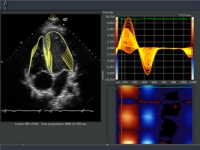

An additional four business units are located in the US. These include Radiation Therapy (OCS, Concord/California), Molecular Imaging (MI, Hoffman Estates/Illinois), Ultrasound (US, Issaquah/State of Washington) and HS (Malvern, Pennsylvania). Internal business units, such as Components (C0), X-ray Tubes/Vacuum Technology (RV), Software Components and Workstations (SW), are the primarily suppliers for the business units mentioned above.